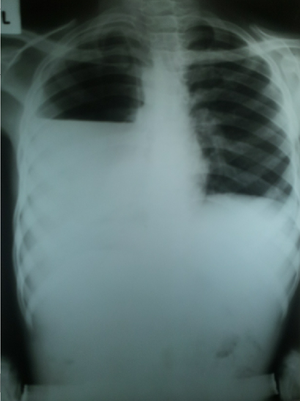

Massive plural effusion

Rt plura mainly

Its hidropneumothorax?

yea